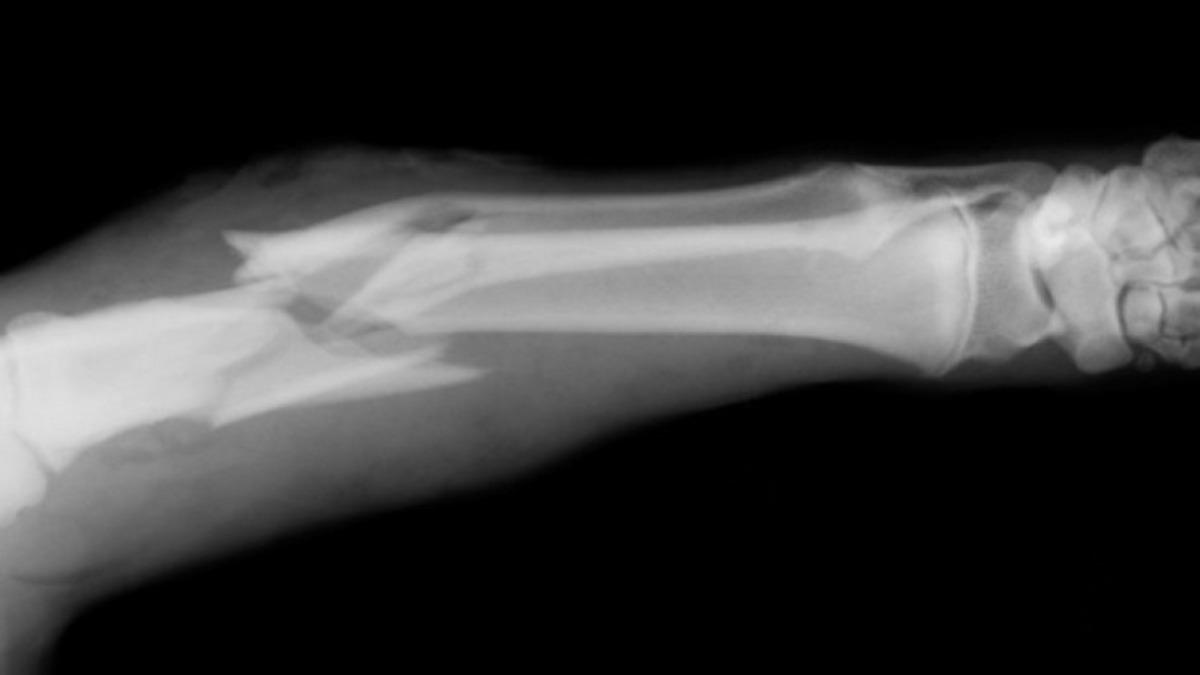

Kemik kırıklarıyla ilgili yüzlerce yıldır hem yanlış bilinen hem de yanlış uygulanan o kadar çok şey var ki... Modern tıbbı tercih etmek yerine günümüzde halen 'kırık çıkıkçı' diye tabir edilen kişilere görünen hastalar dahi mevcut. Vakit kaybetmeden yanlış bildiğimiz 5 gerçeğe göz atıyoruz.

Bu her zaman için doğru değil. Vücudunuza aldığınız herhangi bir darbede kırığı tespit etmek için sorulan bu soru çoğu zaman kırığa işaret etse de bazen kırılan kemiği kımıldatabilmeniz mümkündür. Kırığın bilinen en büyük üç belirtisi şunlardır: Ağrı, şişme ve şekil bozukluğu.